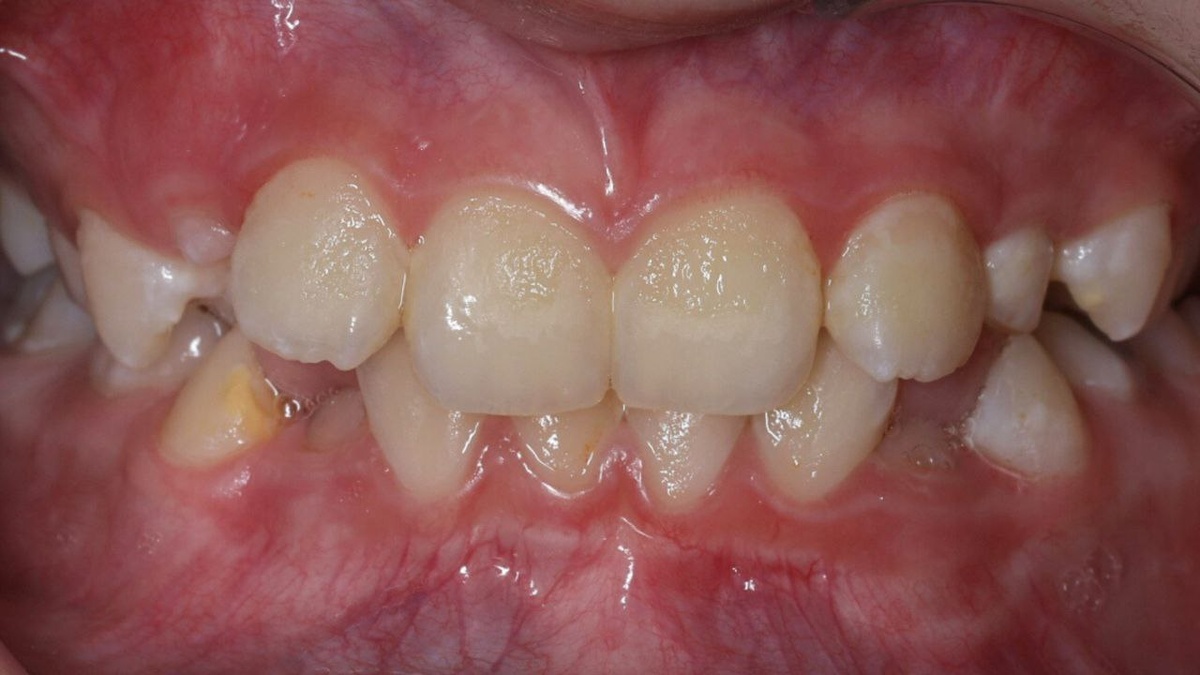

Многие родители замечают, что в период смены прикуса у детей зубы занимают неправильное положение — наклоняются под углом друг к другу, создавая ощущение нехватки места в полости рта. Такую ортодонтическую аномалию называют «скученность зубов», и она является одной из самых частых причин обращений к стоматологу. Почему возникает скученность, можно ли её исправить и к каким последствиям она может привести — рассказала врач-ортодонт клиники «Прайм-стоматология» Шиндяпина Елизавета Васильевна. - Скученное положение зубов — действительно очень распространённая аномалия, при которой нарушается соотношение между величиной челюстей, зубов и их количеством Причин у этой патологии немало: 👉 вредные привычки — закусывание ручки, верхней/нижней губы, сосание пальца, ротовое дыхание могут способствовать неправильному росту и смещению челюстей, деформации зубных рядов. В дальнейшем это нередко вызывает проблемы с жеванием, речью и негативно сказывается на эстетике лица, 👉 полидонтия — наличие св

Многие родители замечают, что в период смены прикуса у детей зубы занимают неправильное положение — наклоняются под углом друг к другу, создавая ощущение нехватки места в полости рта. Такую ортодонтическую аномалию называют «скученность зубов», и она является одной из самых частых причин обращений к стоматологу.

- Скученное положение зубов — действительно очень распространённая аномалия, при которой нарушается соотношение между величиной челюстей, зубов и их количеством